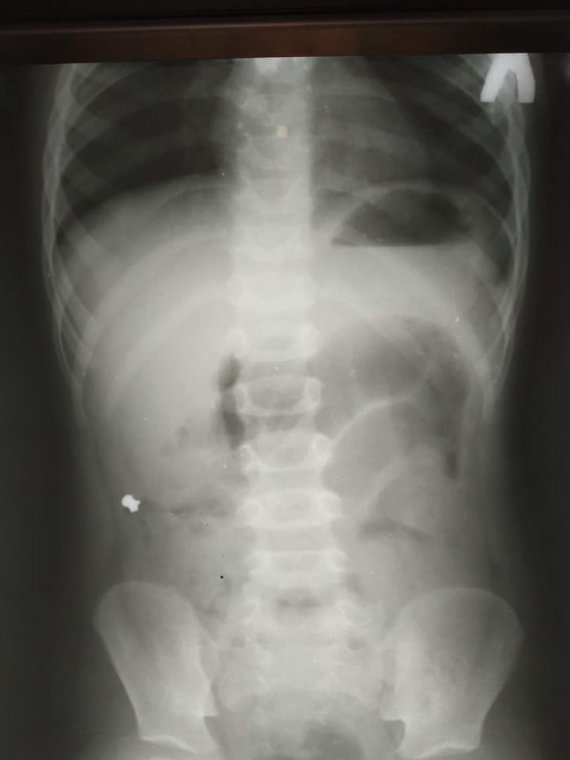

Виявилося, дитина проковтнула кулю для пневматичної гвинтівки. Про це розповіли на сторінці лікарні у Facebook.

"Лікар одразу чітко впізнав обриси кулі від пневматичної гвинтівки. Уточнив у батька хлопчика, чи могло бути, що його син проковтнув кулю. Той пригадав, що в них вдома справді є пневматична рушниця і до неї металеві кулі. Недавно син грався коробкою з кулями. Ймовірно, випадково хлопчик проковтнув одну з них. І все б нічого, якби куля потрапила зі шлунка в кишківник і вийшла", - розповіли в лікарні Охматдит.

Утім куля застрягла в апендиксі дитини й спричинила запалення, через що хлопчику довелось робити операцію.

"Коли ми видаляли апендикс, я побачив, що в ньому є потовщення. Ми його видалили та вже назовні розрізали. Там справді була куля. Вона, як стороннє тіло, потрапила з кишок в апендикс і створила його обструкцію. Це і стало незвичайною причиною апендициту", - розповів дитячий хірург Кирило Лапшин.